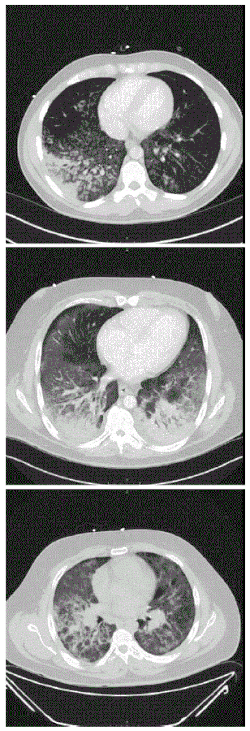

![]() | |

| CT scan of the chest showing diffuse lung infiltrates found in three cases of vaping-associated pulmonary injury | |

There are non-specific laboratory abnormalities that have been reported in association with the disease, including elevations in white blood cell count (with neutrophilic predominance and absence of eosinophilia), transaminases, procalcitonin, and inflammatory markers.[4][66] Infectious disease testing, including blood and sputum cultures and tests for influenza, Mycoplasma, and Legionella were all found to be negative in the majority of reported cases.[66] Imaging abnormalities are typically bilateral and are usually described as "pulmonary infiltrates or opacities" on chest X-ray and "ground-glass opacities" on chest CT.[4]